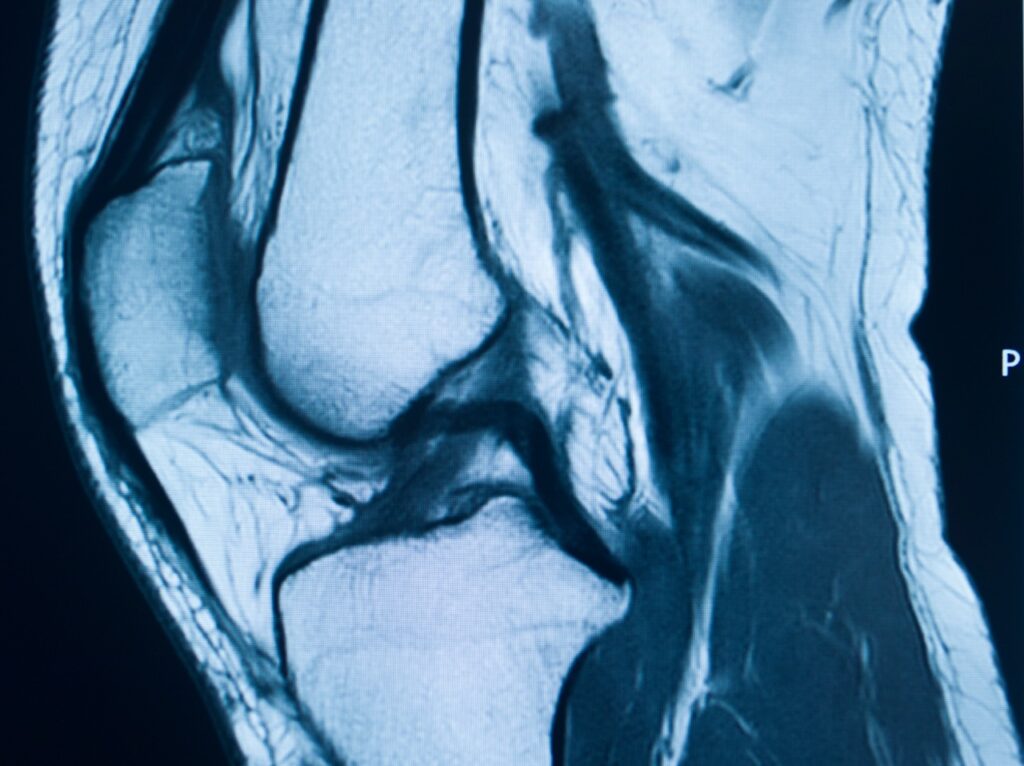

When to Get a Knee MRI for ACL Injury A sudden pop during sports, followed by sharp knee pain, signals something went wrong. Athletes and active individuals know that knee injuries can sideline dreams and daily activities instantly. When your knee swells and feels unstable, you need answers about what’s damaged inside. An ACL tear […]

Knee MRI Florida: Discover How Imaging Reveals the True Cause of Sports Injuries Knee injuries can sideline athletes and active people from the activities they love. One wrong pivot during basketball, a fall while running, or a collision during soccer can cause serious damage. When knee pain persists after an injury, you need answers about […]